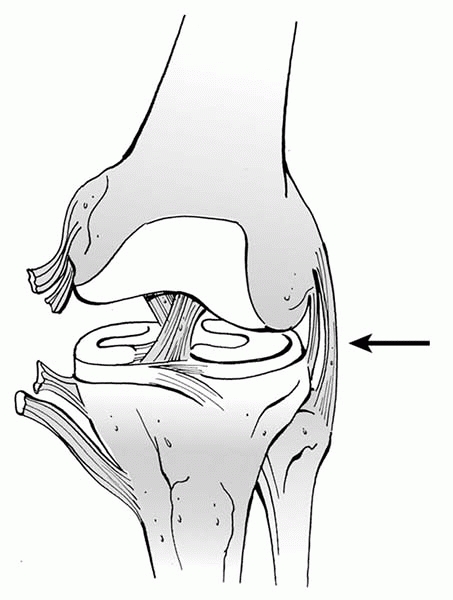

▪ FIGURE 9-4

Injury pattern with closed growth plates. In the mature skeleton, ligaments usually fail before bone when a bending stress is applied across the knee joint, so following a severe valgus stress across the knee a medial collateral ligament (MCL) injury may occur. Black arrow is direction of force. |